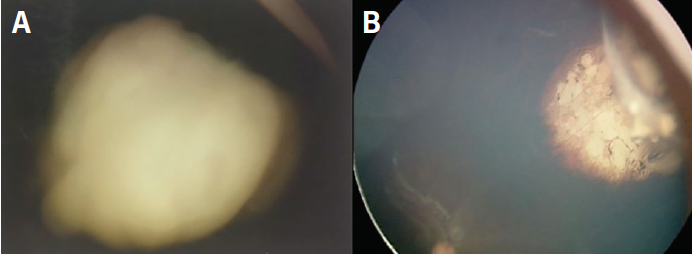

Figure 1. In a 1-year-old child with bilateral retinoblastoma, the right eye was enucleated and the left eye was treated with systemic chemotherapy and laser; a speckled, elevated mass with secondary detachment developed (A). Intrarterial chemotherapy with melphalan, topotecan and carboplatin had a prompt and lasting response without visual compromise (B).

A 1-year-old child presented with bilateral retinoblastoma. The right eye was enucleated. The left eye was treated with systemic chemotherapy and laser (Figure 1A). A speckled, elevated mass with secondary detachment developed below. This is choroidal invasion. The child has only one eye. Should you enucleate?

It is now recognized that isolated choroidal invasion is not a high-risk event and that treatment with modest doses of intravenous chemotherapy may induce resistance in patients with underlying micrometastatic disease. This patient received intraarterial chemotherapy with melphalan, topotecan, and carboplatin, which had a prompt and lasting response without compromising visual function (Figure 1B). No systemic metastases have developed after 2 years of follow-up.